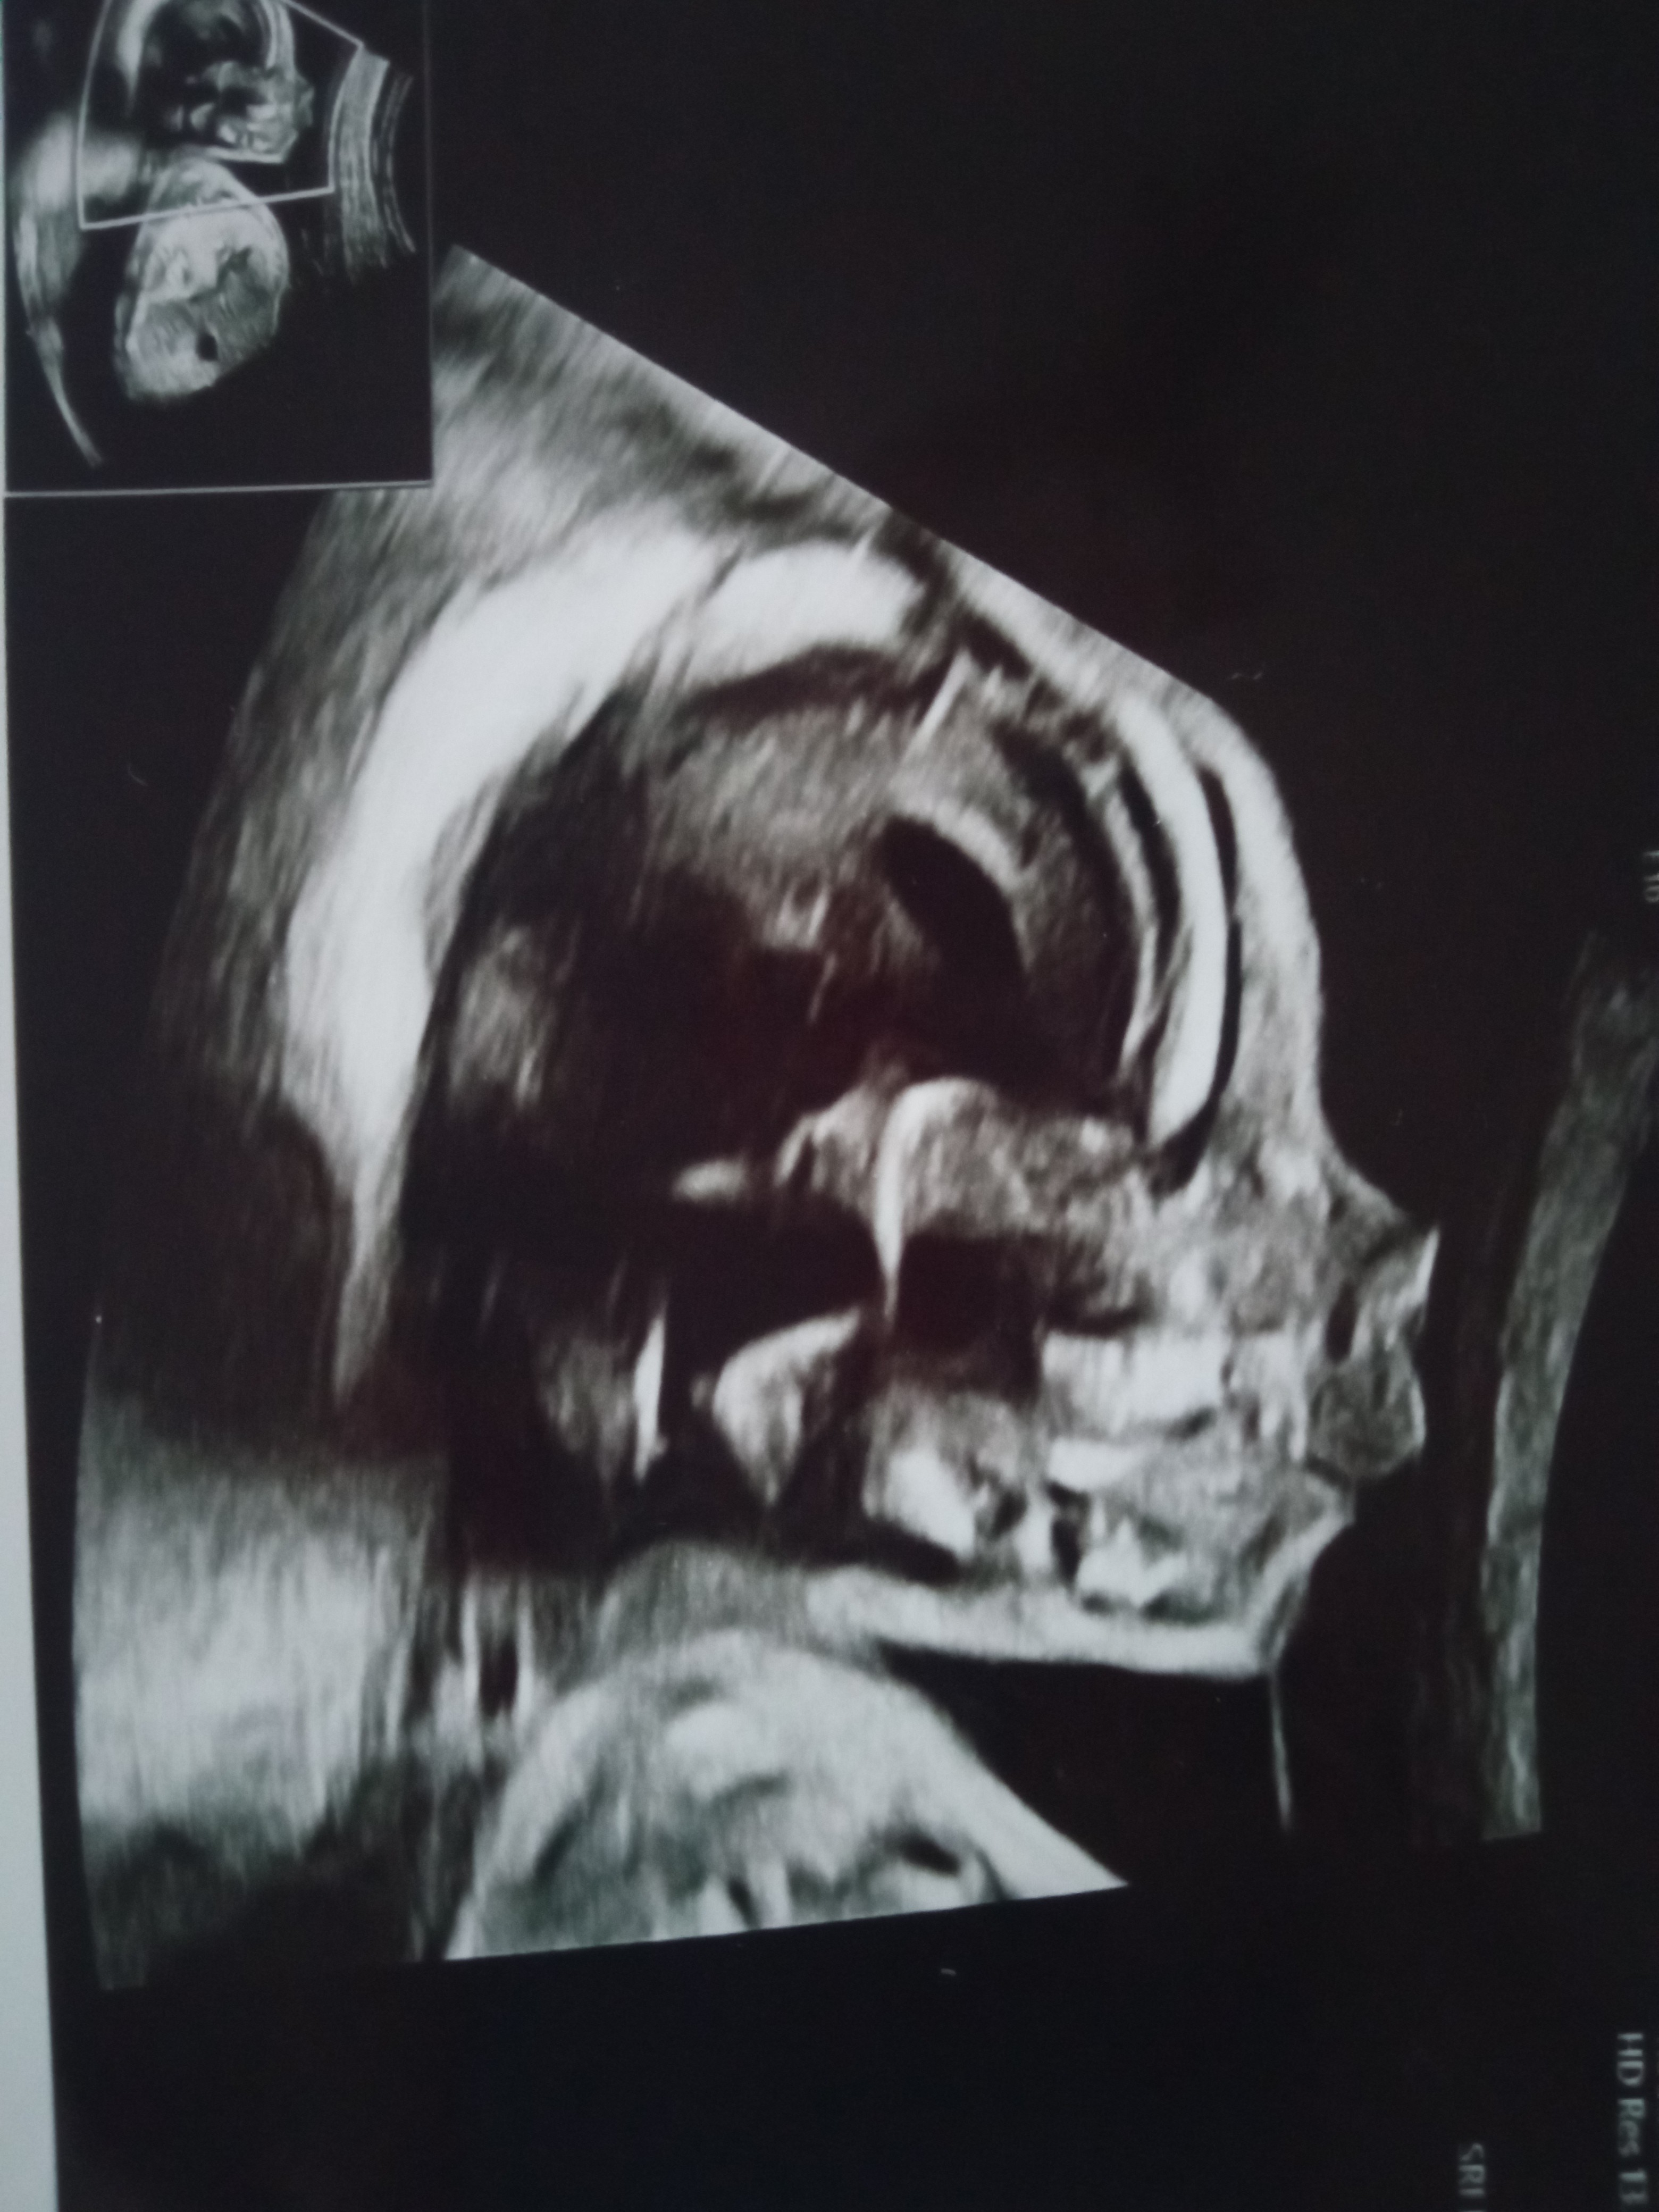

Mam pytanko ,ostatnio w 18 tygodniu robiłam USG i szczeka dziecka wyglądała normalnie a dzisiaj w 19 tygodniu byłam na badaniach prenatalnych i mam wrażenie jakby dziecko miało wysuniętą do przodu górną szczękę.Nie wiem czy po prostu zrobiło taką minę czy coś jest nie tak .Któraś z Was tak miała a dziecko po urodzeniu miało normalną szczękę ?Oba zdjęcia załączam i proszę o odpowiedź.

To nie górna szczęka jest wysunięta tylko żuchwa jest cofnięta - stan fizjologiczny u wszystkich noworodków. Od 6 miesiąca po narodzinach zacznie się powoli wysuwać na właściwe miejsce.